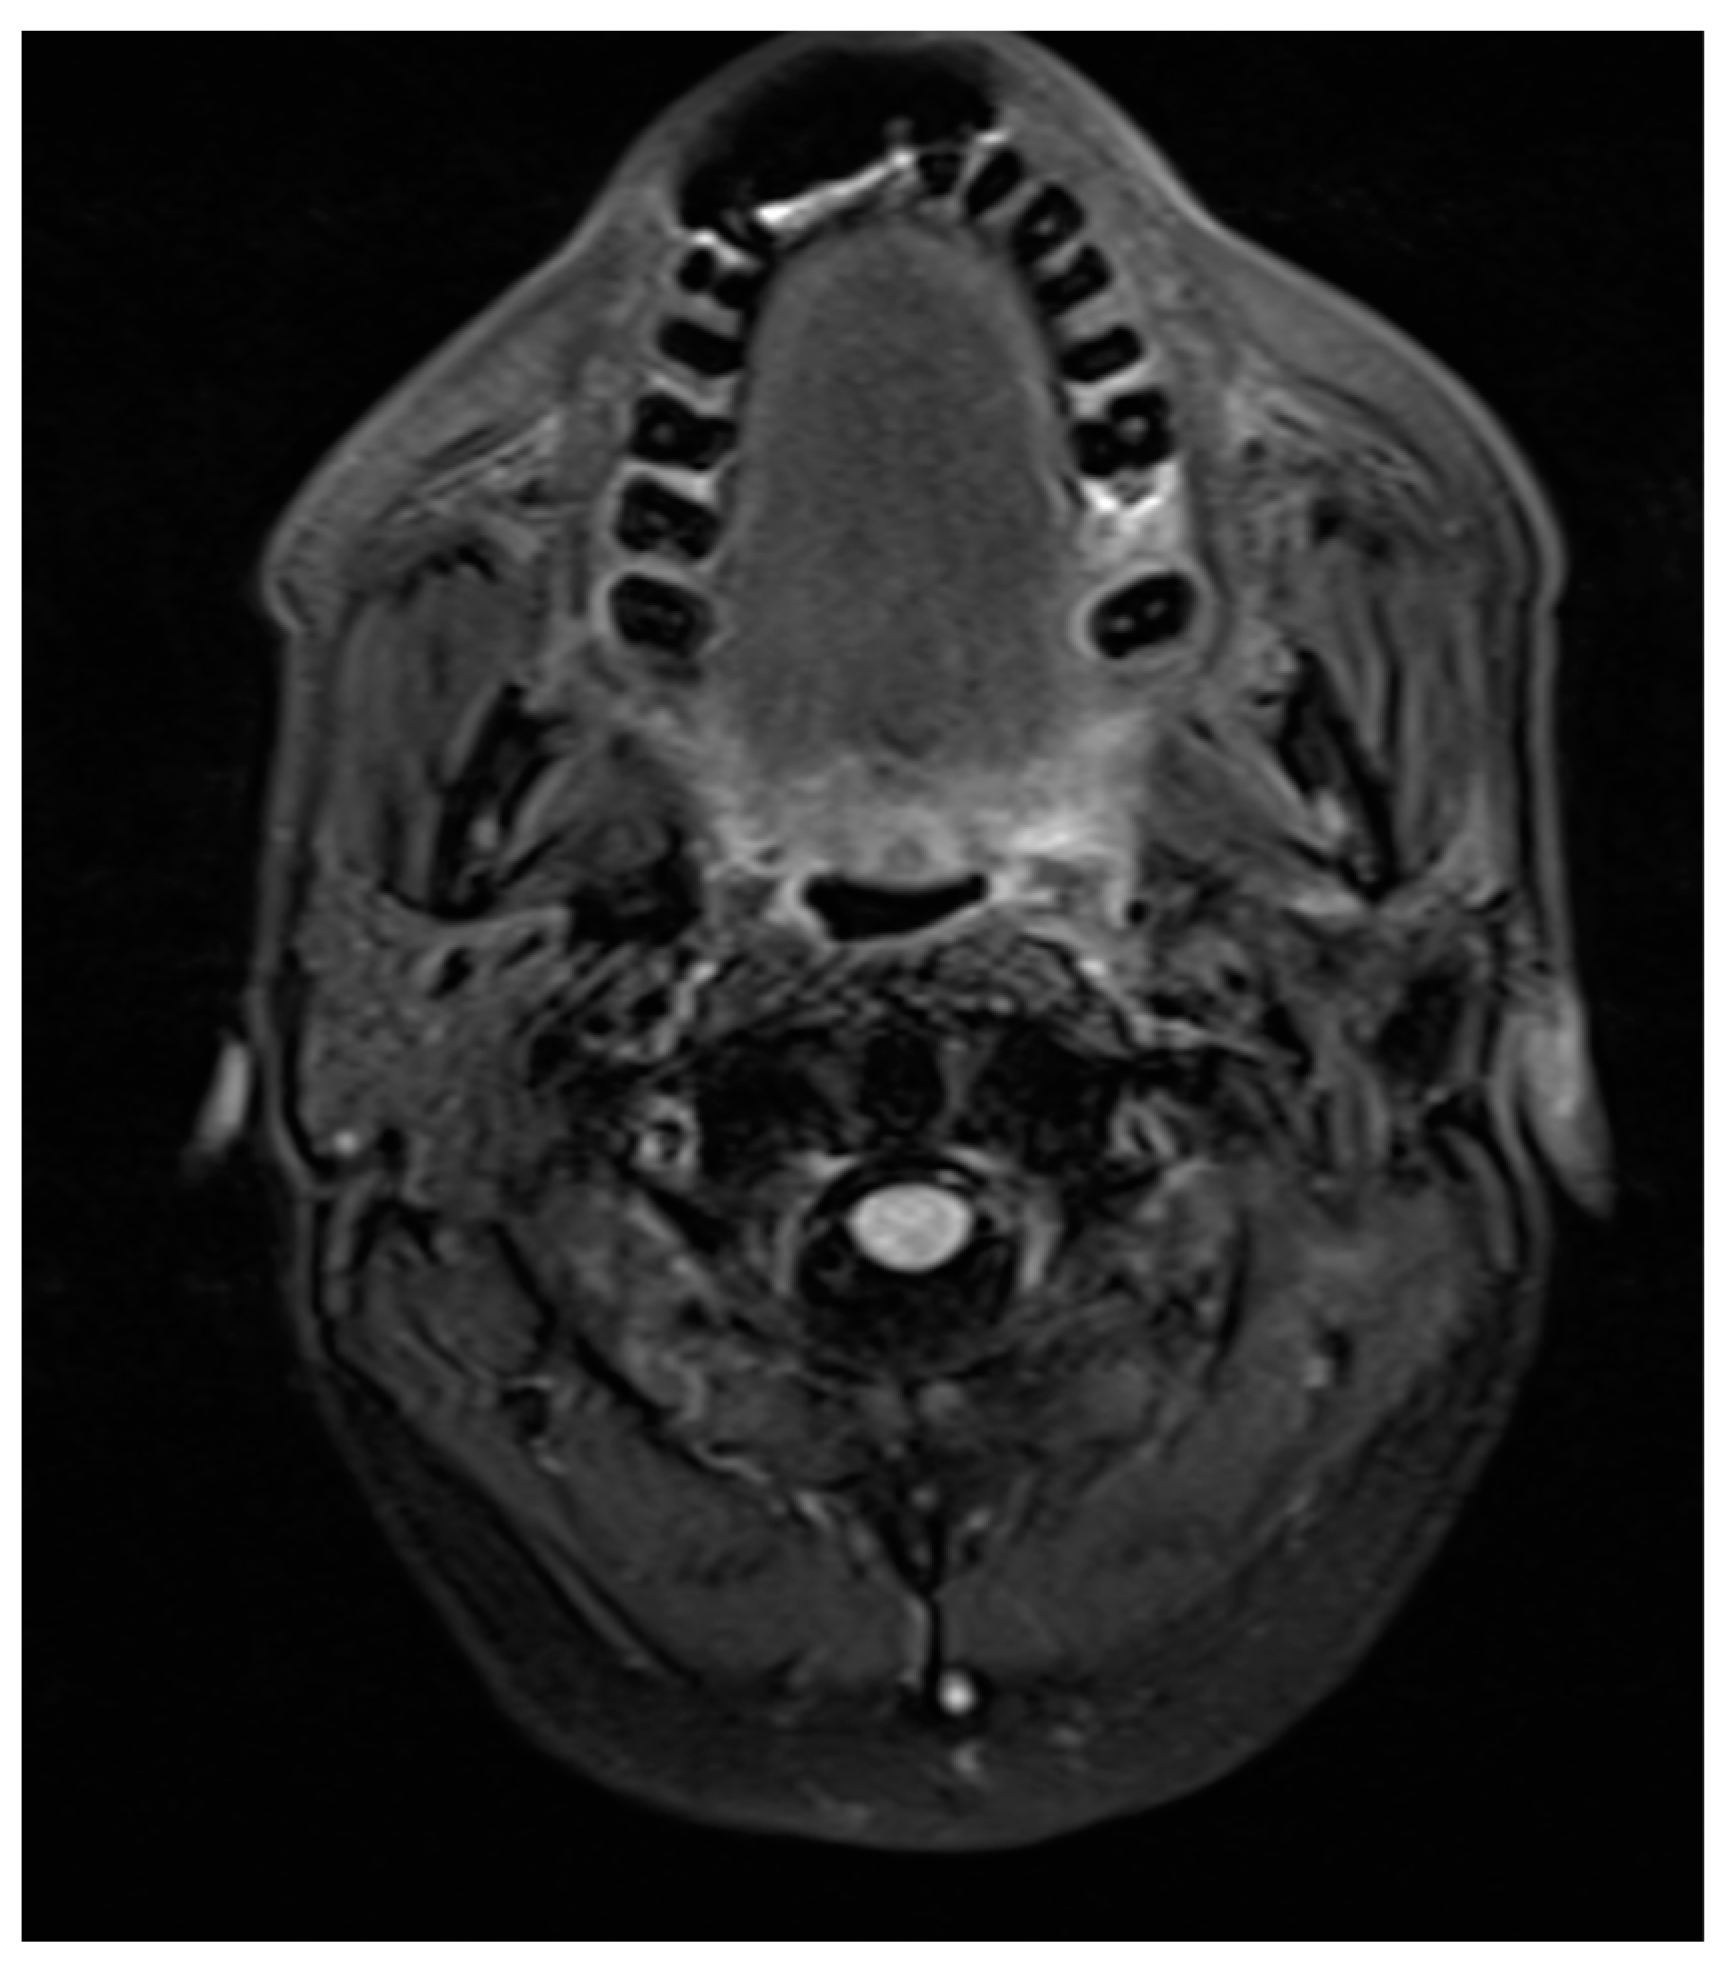

A similar example is presented in the T2 axial section (Figure 9). The porcelain fused to metal fixed prosthesis placed in the mandibular anterior teeth caused a no-signal, presenting anterior artifact extending to the level of the maxillary teeth. This is a particularly inconvenient problem since the MRI imaging was performed to check for any malignant spread in a recurring cancer patient. Although different technical alterations gave us a clue about the region in one plane, it was not sufficient.

Figure 9. T2 weighted image—axial section showing loss of signal in anterior mandible and maxilla due to metal fused crown in mandibular anterior. This obscures the purpose of the MRI, which was performed to identify any malignant spread in a recurring cancer patient.